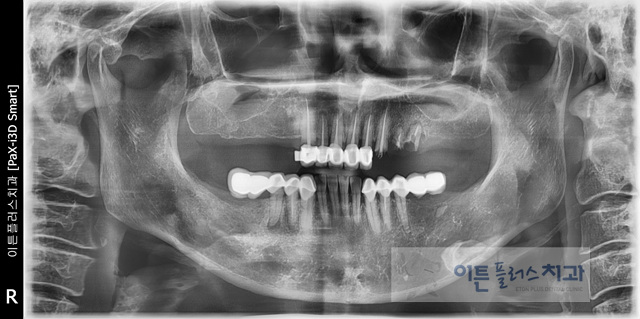

´Ù¼öÀÇ ÀÓÇöõÆ® Ä¡·á

Before

After

¿©·¯ °³ÀÇ ÀÓÇöõÆ®¸¦ ½Ä¸³ÇÏ¿© ´Ù¼öÀÇ Ä¡¾Æ¸¦

¼öº¹ÇÑ ÄÉÀ̽ºÀÔ´Ï´Ù.